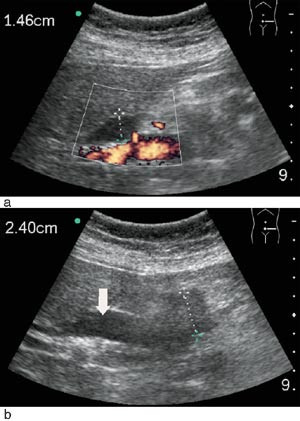

I 81 % av tilfellene fant vi tilfredsstillende bildekvalitet (e-fig 1) med bruk av mobil skanner, til tross for at det hos 28 % av pasientene var dårlig innsyn. Noen syntes at skjermen var for liten og at dette utgjorde en begrensende faktor. Et ultrasonogram hvor man sammenlikner opptak gjort på samme pasienter med Sonosite 180 mot Siemens Elegra demonstrerer hvor bra bildekvaliteten er (fig 2). Gjennomsnittlig tidsbruk under skanning var 7 ± 3 minutter. I 83 % av tilfellene ble den aktuelle kliniske problemstillingen adekvat besvart med mobil skanning, i fire tilfeller (11 %) ble det ansett som nyttig å skanne pasienten med et stasjonært ultralydapparat i tillegg. Utredning og/eller behandling av pasientene ble i 39 % av tilfellene endret som følge av skanning.

Undersøkerens totale tilfredshet med bruk av denne skanneren var: 0 lite tilfreds, 8 % litt tilfreds, 11 % moderat tilfreds, 36 % meget tilfreds, 45 % svært tilfreds. Skanneren var ikke bare egnet til «enkle» problemstillinger, men kunne også gi tilfredsstillende svar på mer kompliserte kliniske og bildemessige utfordringer (fig 3, fig 4).